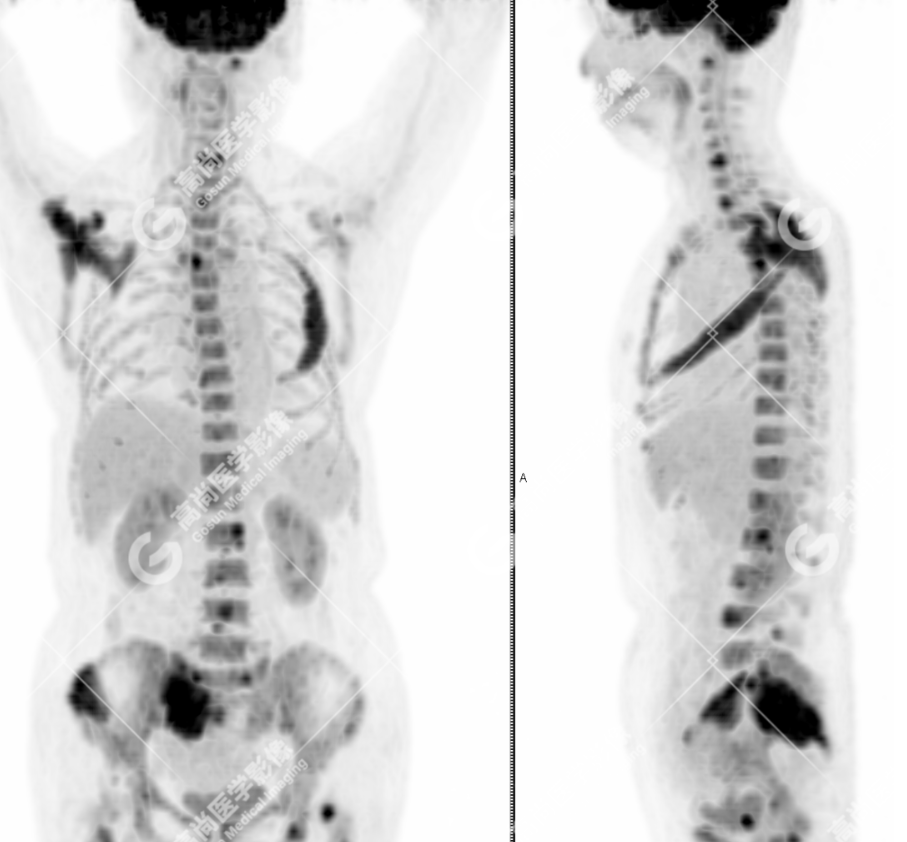

患者,女性,64 岁,因腰痛伴双下肢放射痛 3 月就诊,外院 CT 提示:左侧第四肋骨、右侧肩胛骨及颈 1、6 椎体骨质破坏,考虑转移;于本中心 PET-CT 协诊。既往史:剖宫产;否认外伤史,否认过敏史,否认家族肿瘤史。

颅骨、寰椎前弓左侧份、第 6 颈椎、双侧肩胛骨(右侧为著)、左侧第 4 肋骨、第 1 胸椎、第 4 胸椎、第 2 腰椎及附件、第 4 腰椎及附件、骶骨、右侧髂骨、左侧坐骨结节、左侧股骨颈、双侧股骨小转子等均不同程度骨质吸收、破坏,其中右侧肩胛骨、左侧第 4 肋骨及骶骨右侧份软组织肿块影形成,上述病变均考虑恶性肿瘤(血液系统来源,多发骨髓瘤可能性大),建议右侧髂骨翼穿刺活检明确。

(4)PET-CT 影像表现:在溶骨性破坏区出现相重叠的 18F- FDG 高代谢区;通常呈弥漫性高代谢区。